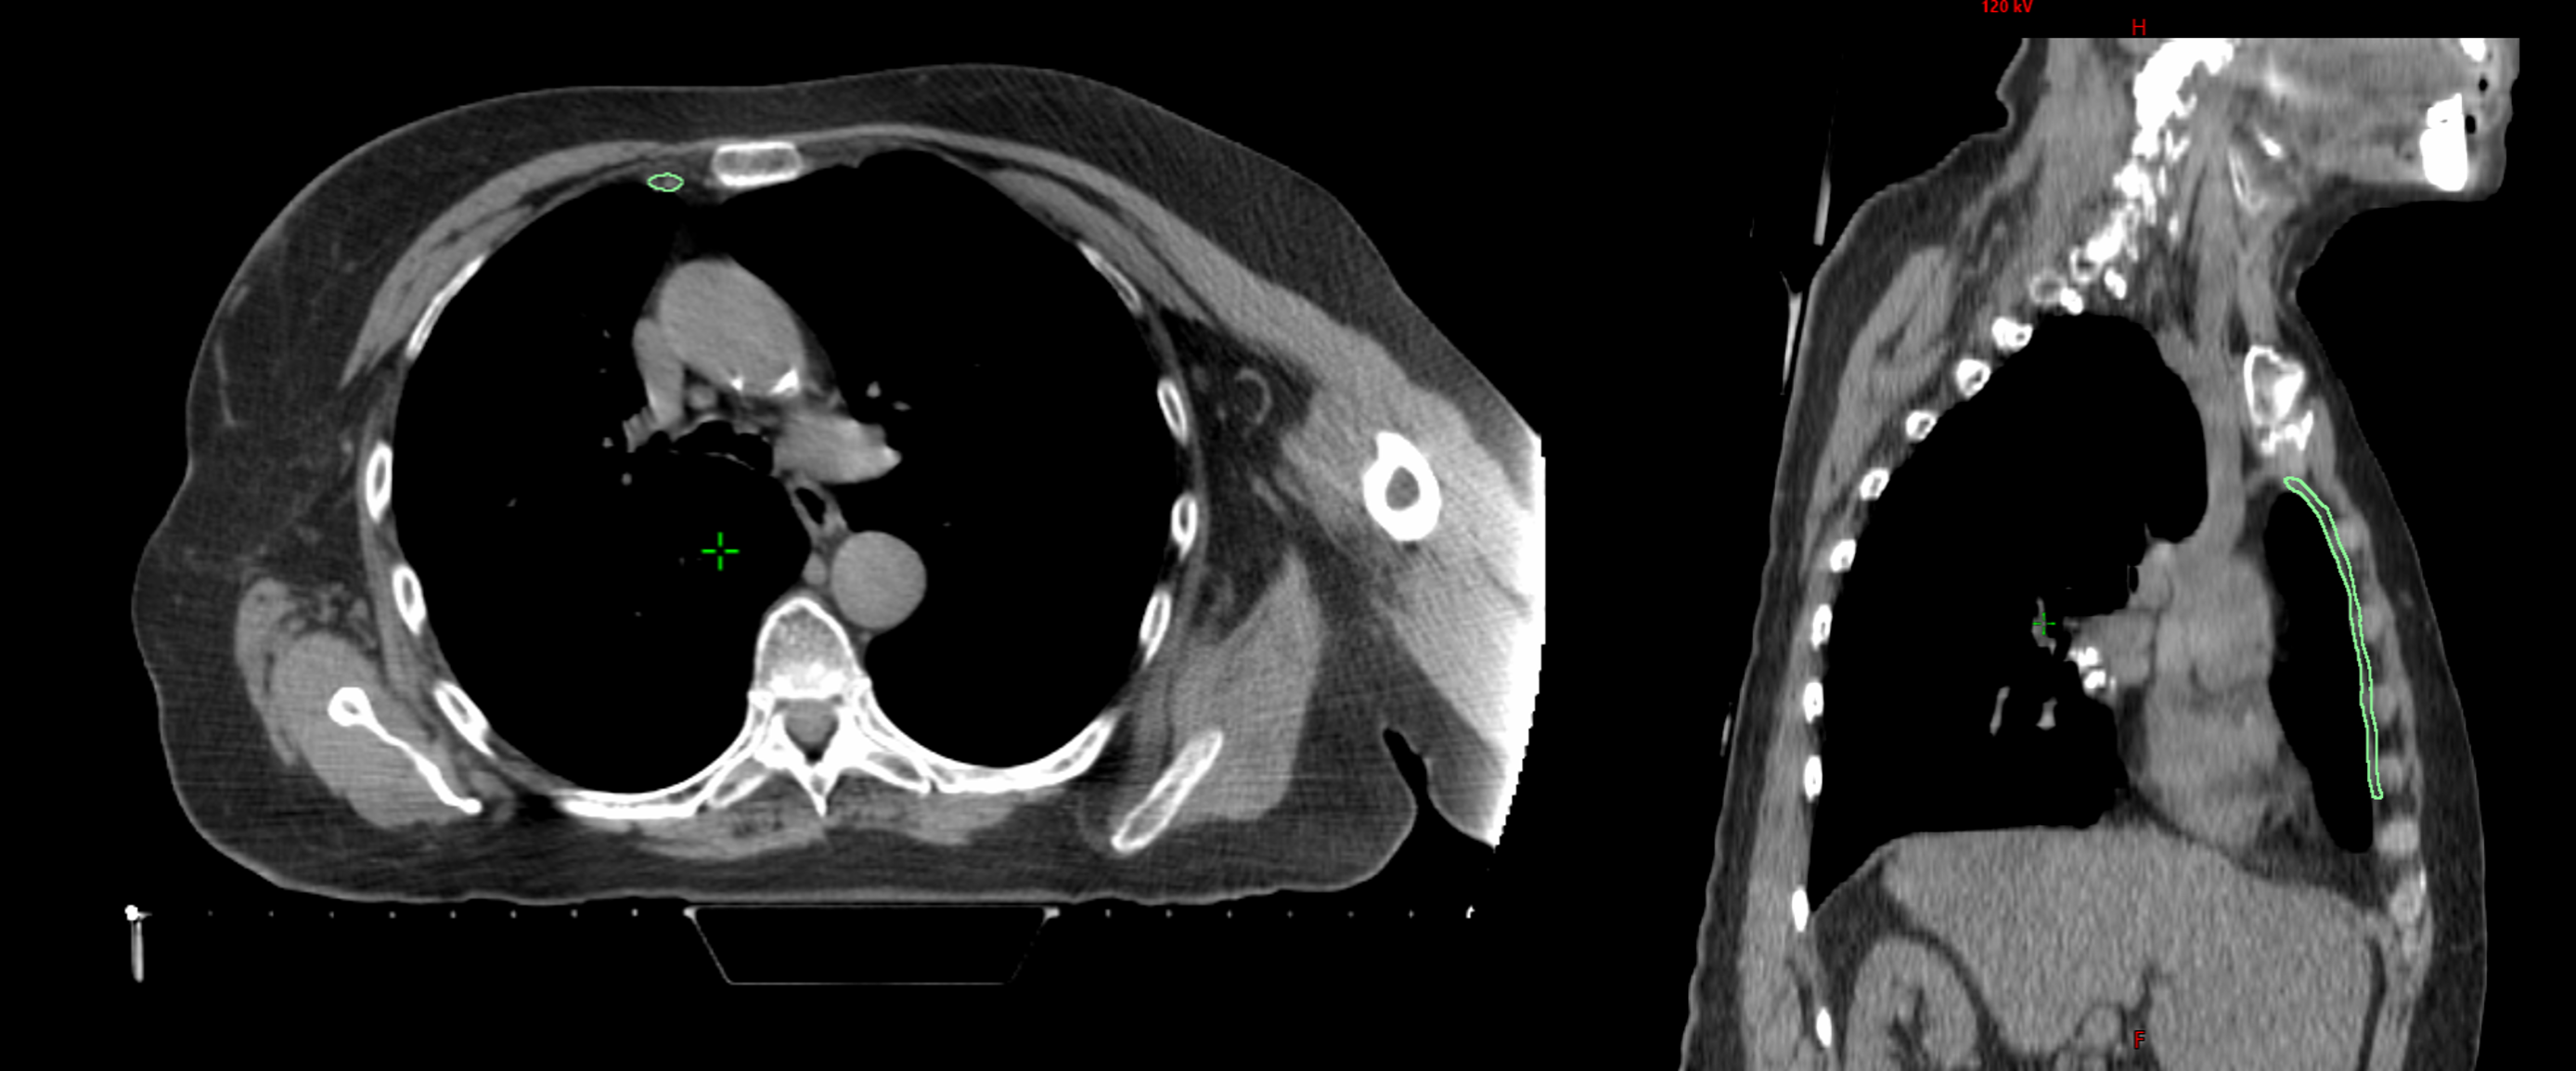

Breast cancer can spread to the internal mammary lymph nodes (IMNs), located near the center of the chest. When involvement is confirmed, IMN irradiation (IMNI) can improve outcomes; however, its use in low-risk patients remains controversial due to potential radiation exposure to the heart, lungs, and contralateral breast. This project contributes to a retrospective population study at BC Cancer investigating how primary tumor location and IMN radiation dose relate to survival outcomes. To support this research, a data pipeline is being developed to automate the import and segmentation of approximately 19,000 patient CT datasets (2005–2014) using Limbus Contour, a deep learning-based auto-segmentation software. My contributions include developing C# scripts for contour transfer and a QA system to evaluate the accuracy of AI-generated contours for future pipeline integration.

- Method A: Compared AI contours against clinical contours. This was unreliable due to inconsistent guidelines (RTOG vs ESTRO) and incomplete slices.

- Method B: Compared AI contours to a reviewed subset of 100 Limbus-generated contours (RTOG guideline), providing a consistent baseline.